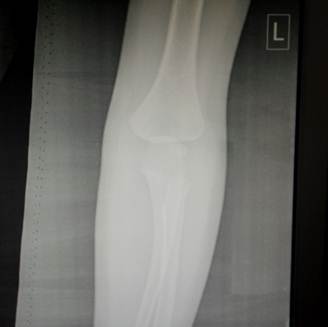

11- 13 лет

Это возраст, в котором все ядра окостенения достигли максимального

развития и приняли формы соответсвующих образований. На рентгенограммах их

разделяют узкие полоски ростковых зон. Это максимальный расцвет детского локтя.

Возраст

12 лет. Все ядра окостенения локтя развиты и разделены узкими хрящевыми

прослойками. Вершина локтевого отростка содержит основное ядро окостенения и

ядро – спутник неправильной формы.

14 лет. Стремительное закрытие зон роста локтевого сустава. Можно заметить

узкие просветы в основании медиального и латерального надмыщелков, а также пока

еще открытую зону роста в локтевом отростке.